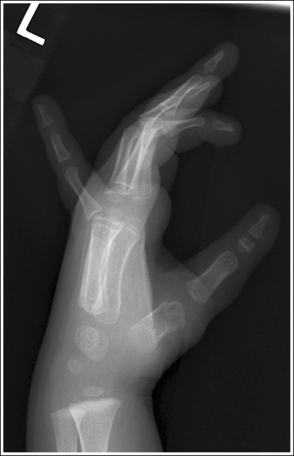

Hand: “Fan” Lateral Projection (Lateromedial)

See Figure 4-27 and Box 4-10.

Density is adequate to demonstrate the surrounding metacarpal soft tissue and bony structures of the hand.

• For the fan lateral hand projection, it is difficult to demonstrate the phalanges and the metacarpals with optimal density simultaneously because of the difference in thickness between the two body parts when the fingers are separated. Evaluate the requisition to determine which anatomy of the hand is of interest so that the mAs can be adjusted to obtain optimal density in that area.

The second through fifth digits are separated, demonstrating little superimposition of the proximal bony or soft tissue structures. The thumb is demonstrated without superimposition of the other digits. Its position may vary from a PA projection to a slight PA oblique projection.

• For a lateral hand projection, place the medial hand surface resting against the IR; then fan or spread the fingers as far apart as possible without superimposing the thumb. The fingers are fanned most effectively by drawing the second and third fingers anteriorly and the fourth and fifth fingers posteriorly. The amount of finger separation obtained will depend on the patient's mobility (Figure 4-28). Immobilization devices are available to help maintain proper positioning. When the fingers are fanned, they can be individually studied. If the fingers are not adequately separated, they superimpose one another on the image (see Images 26 and 28).

The second through fifth metacarpals are superimposed.

• Superimpose the second through fifth metacarpals by palpating the patient's knuckles and placing them directly on top of one another.

• Verifying a lateral hand projection. On a lateral hand projection, a true lateral wrist position, represented by superimposition of the ulna and radius, is not always accomplished when the metacarpal midshafts are superimposed. Instead, the ulna is demonstrated slightly posterior to the radius. Because of this variation, a true lateral projection of the hand should be determined by judging the degree of superimposition of the second through fifth metacarpal midshafts and not the degree of ulnar and radial superimposition. If the metacarpal midshafts are not superimposed and the fifth metacarpal is demonstrated anterior to the second through fourth metacarpals, the hand was slightly externally rotated or supinated (see Image 26). The fifth metacarpal can be identified by its length; it is the shortest of the second through fifth metacarpals. If the metacarpal midshafts are not superimposed and the second metacarpal is demonstrated anterior to the third through fifth metacarpals, the hand was slightly internally rotated or pronated (see Images 27 and 28). The second metacarpal can also be identified by its length; it is the longest.

The IP joints are open, and the phalanges are not foreshortened.

• The IP joint spaces are open and the phalanges are visible without foreshortening when the thumb is depressed and all the digits are positioned parallel with the IR.

The MP joints are at the center of the exposure field. The distal, middle, and proximal phalanges, the metacarpals, the carpals, and approximately 1 inch (2.5 cm) of the distal radius and ulna are included within the collimated field.

• Center a perpendicular central ray to the second MP joint to place it in the center of the collimated light field. Once the central ray is centered, open the longitudinal collimation to include the distal phalanges and the distal forearm. Transversely collimate to within 0.5 inch (1.25 cm) of the first and fifth finger's skin line.